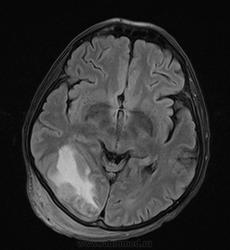

Мужчина проходит курс химиотерапии по поводу Т-клеточной лимфомы с первичным поражением кишечника (гистологическая верификация). За последний месяц - появление множественных очагов в печени, а также необычных изменений в голове.

- бесформенное образование в мягких тканях затылочной области, накапливающее контраст;

- утолщение твердой мозговой оболочки в той же области с накоплением контраста по пахименингиальному типу;

- отек прилежащей мозговой ткани с геморрагическими изменениями в коре, сопровождающийся масс-эффектом.

Мое мнение это лимфома кожи с прорастанием (если так можно сказать) через перфорирующие сосуды в ТМО, с кровоизлияниями в коре за счет повреждения сосудов. Либо это лептоменингальнаые проявления лимфомы. Больше на ум ние чего не приходит. Хотелось бы услышать мнение более опытных специалистов. но все почему-то молчат...

Я тоже думаю, что это лимфома. Думаю, не так важно, прорастает ли она из мягких тканей в мозговые оболочки, или наоборот. Только поражение мозговой оболочки - это пахи-, а не лептоменингиальные изменения.

В таком случае изменения в мозговой ткани - это отек, обусловленный нарушением венозного оттока по поверхностным венам; думаю, вкупе с геморрагическими изменениями этот отек можно квалифицировать как венозный инфаркт.